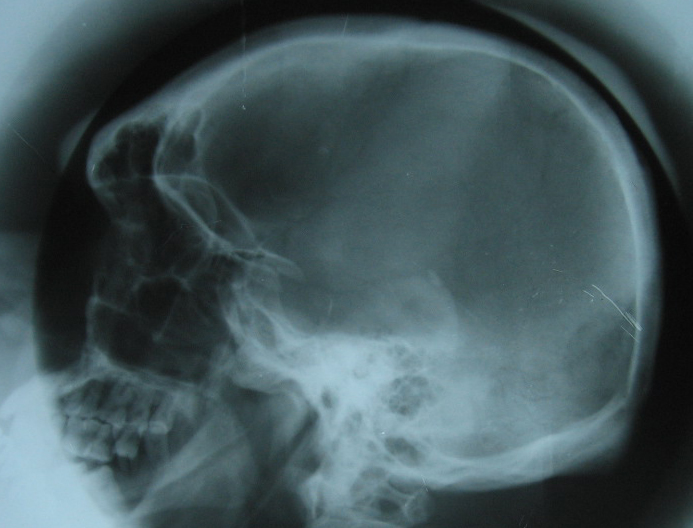

acromegaly skull lateral